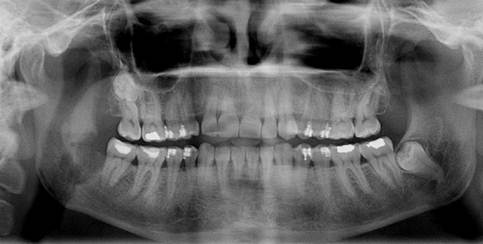

Under local anesthesia, a flap was reflected to completely reveal the buccal bony plate to the apical extent of the roots. Under constant saline cooling, a round burr was used to penetrate the cortical bony plate from the cementoenamel junction to the tooth apex. Due to the position of the third molar, the external oblique ridge was also flattened with the burr to provide sufficient visibility. During the attempt to luxate the tooth using a straight bein elevator between the second and third molars with a normal application of force, a cracking noise was heard. A panoramic radiograph was taken immediately, revealing a non-displaced, unfavorable green-stick-like fracture line extending from the base of the alveolar margin to the lower mandibular border (Fig. 2).

Perioperative x-ray of the patient showing the thin fracture line.